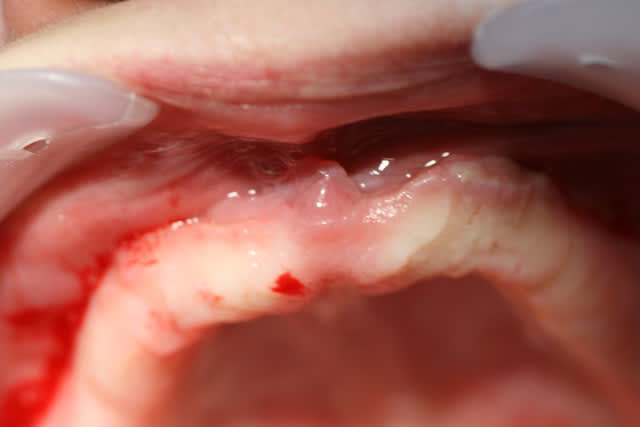

Nouvelle patiente qui souhaite refaire son complet maxillaire, qui est moche, fissuré, goudronné mais stable.

Sous la prothèse, hyperplasie gingivale bilatérale palatine.

Y-a-t-il une alternative à la chirurgie?

Img 20170125 090002 ps48gf - Eugenol

4a338550 6a5b 47ea b2a7 d3cb675c5076 oni5gh - Eugenol